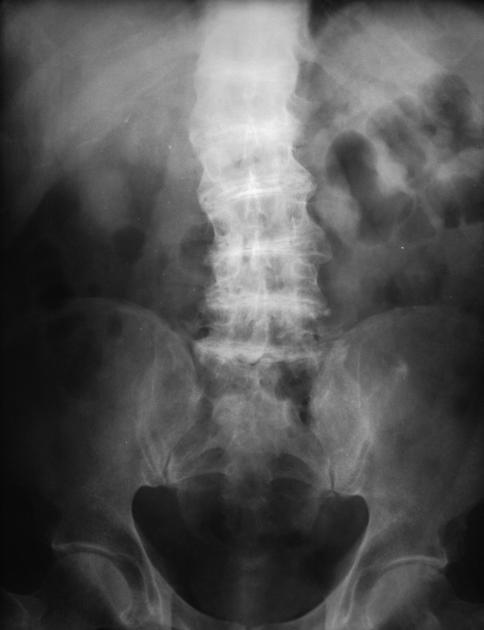

Medullary nephrocalcinosis is more common than

cortical nephrocalcinosis

DDX for medullary nephrocalcinosis